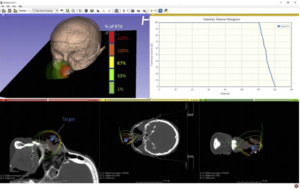

Optimizing Timing of Immunotherapy Improves Control of Tumors by Hypofractionated Radiation Therapy

Publication: PLoS One. 2016 Jun 9;11(6):e0157164. PMID: 27281029 | PDF Authors: Young KH, Baird JR, Savage T, Cottam B, Friedman D, Bambina S, Messenheimer DJ, Fox B, Newell P, Bahjat KS, Gough MJ, Crittenden MR. Institution: Earle A. Chiles Research Institute, Robert W. Franz Cancer Center, Providence Portland Medical Center, Portland, OR, USA. Background/Purpose: The anecdotal reports of promising results seen with immunotherapy and radiation in advanced malignancies have prompted several trials combining immunotherapy and radiation. However, the ideal timing of immunotherapy with radiation has not been clarified. Tumor bearing mice were treated with 20Gy radiation delivered only to the tumor combined with either anti-CTLA4 antibody or anti-OX40 agonist antibody. Immunotherapy was delivered at a single timepoint around radiation. Surprisingly, the optimal timing of these therapies varied. Anti-CTLA4 was most effective when given prior to radiation therapy, in part due to regulatory T cell depletion. Administration of anti-OX40 agonist antibody was optimal when delivered one day following radiation during the post-radiation window of increased antigen presentation. Combination treatment of anti-CTLA4, radiation, and anti-OX40 using the ideal timing in a transplanted spontaneous mammary tumor model demonstrated tumor cures. These data demonstrate that the combination of immunotherapy and radiation results in improved therapeutic efficacy, and that the ideal timing of administration with radiation is dependent on the mechanism of action of the immunotherapy utilized. Funding:

Combination immunotherapy and radiation therapy of spontaneous mammary tumors in immune competent mice. (a) MMTV-PyMT tumors were harvested from approximately 100 day old female MMTV-PyMT+ mice, the tumor disrupted ex vivo and 1x106 viable cells injected orthotopically into immunocompetent syngeneic FVB mice. (b) Mice with d14-d17 tumors underwent CT-guided radiation therapy (RT) using a Small Animal Radiation Research Platform and i) images used to place isocenters within individual mammary tumors and collimeters and beam angles designed to deliver focal radiation to the tumor and minimal dose to radiosensitive organs. ii) CT images were segmented by tissue density and this information used to predict dose delivery. Mice were also randomized to receive 250μg anti-CTLA4 immunotherapy 7d prior to RT, and 250μg anti-OX40 immunotherapy d1 and d4 following radiation. (c) Graphs show i) average tumor growth and ii) overall survival. |